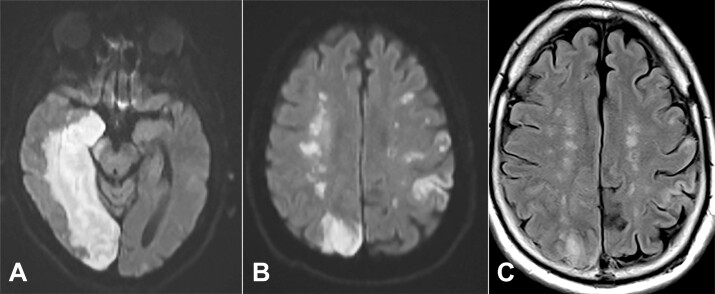

内分水岭梗死(IWIs)发生在大脑深动脉和浅动脉分支的交界处。尽管在放射学文献中有记录,但在尸检时很少遇到IWIs。在这里,我们报告一个59岁的被监禁的男性,他被发现在他的监狱牢房的地板上没有反应后被带到急诊室。初步检查和影像学表现分别为右侧偏瘫、失语、右侧面部下垂和左侧大脑中动脉严重狭窄。入院后4天和死亡前26天的重复成像显示,右侧颈内动脉交通段颅内严重狭窄,右侧大脑后动脉区域出现大面积急性梗死,双侧深部白质缺血性改变,右侧呈“玫瑰状”损伤,这是典型的IWIs。死后大体检查显示右侧深部白质病变已发展为融合性“雪茄状”亚急性IWI,累及右侧辐射冠。这是第一例有充分文献证明的IWI病例,影像学和大体病理相关联。本病例独特地突出了尸检时罕见的病变,并提供了内部分水岭神经解剖学的良好视觉表现。

Internal watershed infarcts (IWIs) occur at the junction of the deep and superficial perforating arterial branches of the cerebrum. Despite documentation in the radiology literature, IWIs are rarely encountered at the time of autopsy. Here, we report the case of a 59-year-old incarcerated male who was brought to the emergency department after being found unresponsive on the floor of his jail cell. Initial examination and imaging demonstrated right-sided hemiplegia, aphasia, right facial droop, and severe stenosis of the left middle cerebral artery, respectively. Repeat imaging 4 days after admission and 26 days before death demonstrated advanced stenosis of the intracranial, communicating segment of the right internal carotid artery, a large acute infarct in the right posterior cerebral artery territory, and bilateral deep white matter ischemic changes with a right-sided "rosary-like" pattern of injury that is typical of IWIs. Postmortem gross examination showed that the right deep white matter lesion had progressed to a confluent, "cigar-shaped" subacute IWI involving the right corona radiata. This is the first well-documented case of an IWI with radiologic imaging and photographic gross pathology correlation. This case uniquely highlights a rarely encountered lesion at the time of autopsy and provides an excellent visual representation of internal watershed neuroanatomy.